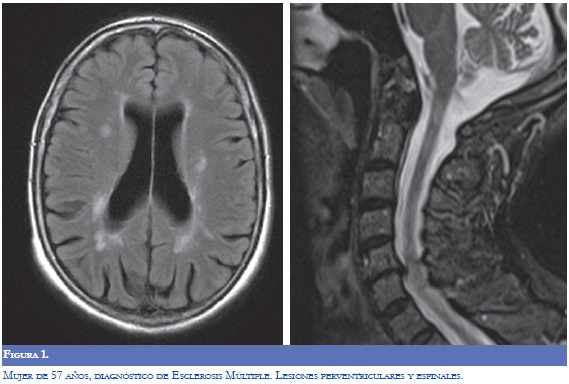

La RM (Figuras 1-4) permite valorar mejor la sustancia blanca cerebral y se pueden ver lesiones pequeñas de causas isquémicas que se presentan en el LES/SAF hasta en 30 a 70% y se asemejan a las placas desmielinizantes de la EM (2). El concepto de realce con gadolinio que sugiere inflamación no es específico para la EM, los complejos inmunes inducen la alteración de la barrera hematoencefálica, de modo que la RM como método diagnóstico no permite definir la causa. La distribución de las lesiones pueden orientar al diagnóstico y las lesiones subcorticales prevalecen en el LES/SAF y las periventriculares próximas al cuerpo calloso como lesiones ovoides (dedos de Dawson) y los hoyos negros son característicos de la EM. La evolución de las lesiones en diferentes secuencias de RM es de ayuda para la diferenciación y se consideran de evolución dinámica en la EM y en cambio permanecen estáticas en el LES con o sin SAF y mejoran con la anticoagulación (2).